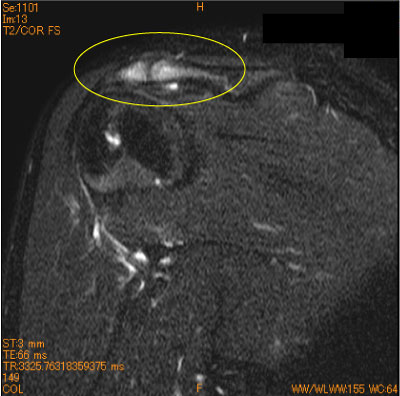

Os acrominaleの損傷、骨浮腫-肩関節MRI-

10代男性。陸上競技部。 「肩が鳴る」との訴え。

周囲の骨浮腫、症状から、損傷と診断された。

読影に慣れていないと、冠状断で肩鎖関節と見間違う。

![]() Obl. Cor T2WI 脂肪抑制 |

Axial T2WI 脂肪抑制 |